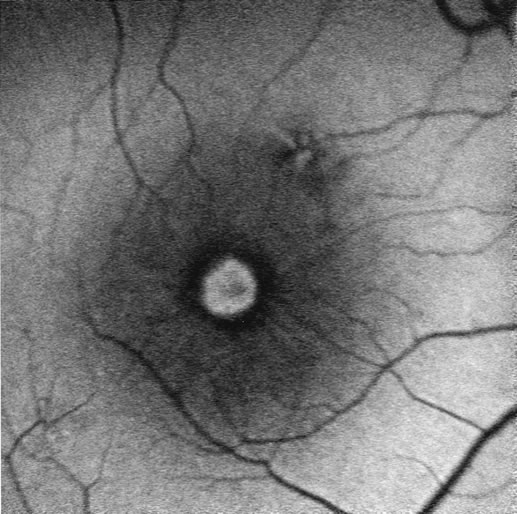

The differentiation of a partial-thickness, or lamellar, macular hole from a full-thickness macular hole can be challenging, and FA is often helpful in assisting in the diagnosis.55 As in a full-thickness hole, a lamellar hole presents as an excavation of the retina, and the presence of drusen underneath the lamellar hole can simulate the yellow deposits seen at the base of full-thickness holes. Occasionally, there is a full-thickness hole at one side of a lesion, and the rest of the lesion consists of a lamellar defect. FA will show immediate hyperfluorescence from the choroidal circulation under a full-thickness hole (Fig. 34A), whereas a lamellar hole, with a relatively intact RPE, will block some of the normal fluorescence from the choriocapillaris (Fig. 34B).

Fig. 34. Full-thickness and partial macular holes. A. There is a discrete hole in the central macula. Hyperfluorescence reflects choriocapillaris leakage that is normally partially blocked by retinal pigment epithelium. B. There is partial blockage of the choroidal hyperfluorescence, but subtle hyperfluorescence is visible. (Courtesy of Dr. Peter Judson.)